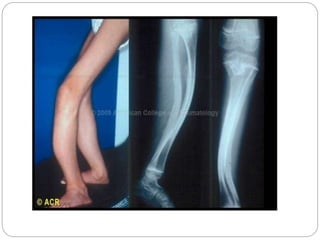

 Curved Limbs.

XRAY

 Generalized osteopenia

 Thinning of long bones

 #s in various stages of healing

 Vertebral compression & spinal #

 Skull enlarged, presence of wormian bone

CLINICAL FEATURES  Propensityto fracture even with minor trauma, often without pain and swelling  Fracture recur throughout childhood  Callus formation is florid  New bone is abnl,remains‘plaible’- malunion  By 6yrs-deformities of long bones, vertebral compression # →kyphoscoliosis

XRAY  Generalized osteopenia Thinning of long bones  #s in various stages of healing  Vertebral compression & spinal #  Skull enlarged, presence of wormian bone